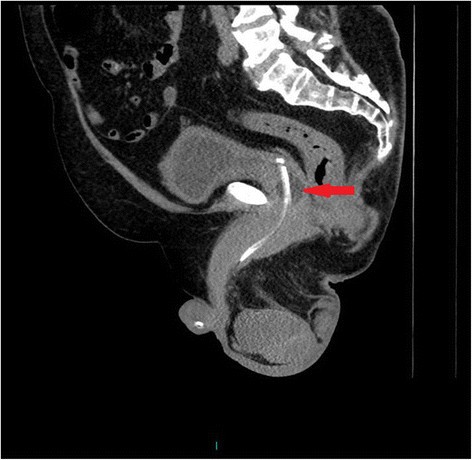

Figure 4From: Missed signs of autonomic dysreflexia in a tetraplegic patient after incorrect placement of urethral Foley catheter: a case reportThe tip of Foley catheter, which is radio-opaque, is not lying within the urinary bladder but it is located distal to bladder neck. The balloon of Foley catheter (arrow) is seen outside the urinary bladder within the urethra.Back to article page